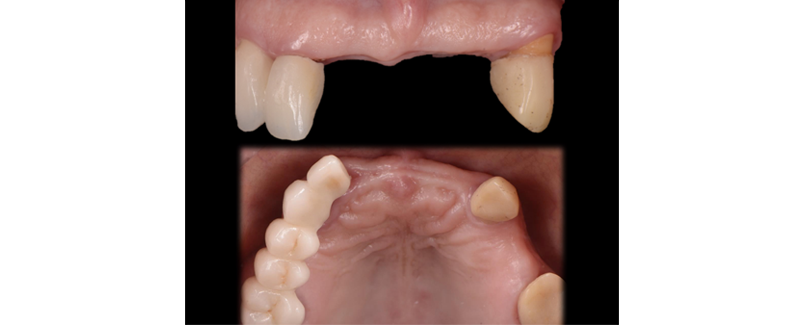

If four or more teeth remain in one arch and are structurally and biologically sound, the benefit of retaining them needs to be carefully evaluated and considered. (Fig. 3)